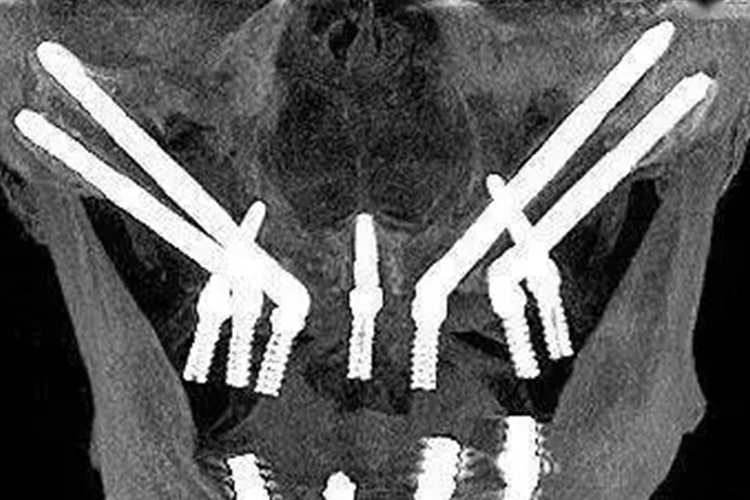

穿颧骨种植牙为颧骨种植体技术,可通过切开上颌软组织后直接植入颧骨内,或者通过穿上颌骨途径将种植体植入颧骨内。颧骨种植体由钛或钛合金制成,直径一般为3.4-4.0mm,长度为30-50mm。穿颧骨种植牙可与常规种植体联合修复,治疗患者多处牙列缺失症状。

颧骨种植体指的是植入颧骨的种植体,主要用于上颌骨萎缩严重的患者。上颌前部骨量不足可能导致种植体穿入鼻腔,而后部骨量不足则可导致种植体穿入上颌窦并造成一系列并发症,因此患者还需要在种植前进行上颌窦提升术、植骨术及骨牵引成骨术等,创伤大、时间长、并发症多。